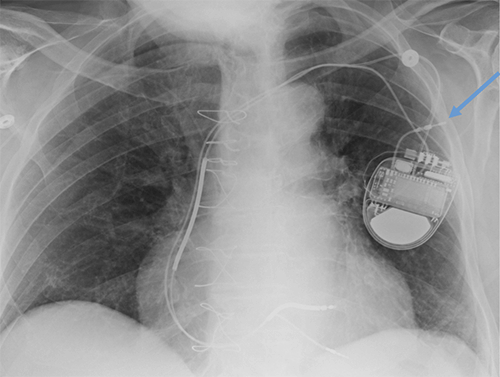

- CEID images with lead types:

Pacemaker with transvenous leads

Pacemaker with epicardial leads

Defibrillator lead

Subcutaneous defibrillator

Cut epicardial wires (often hard to see)

Abandoned leads

Abanded leads plus generator

Temporary transvenous lead

Leadless pacemaker